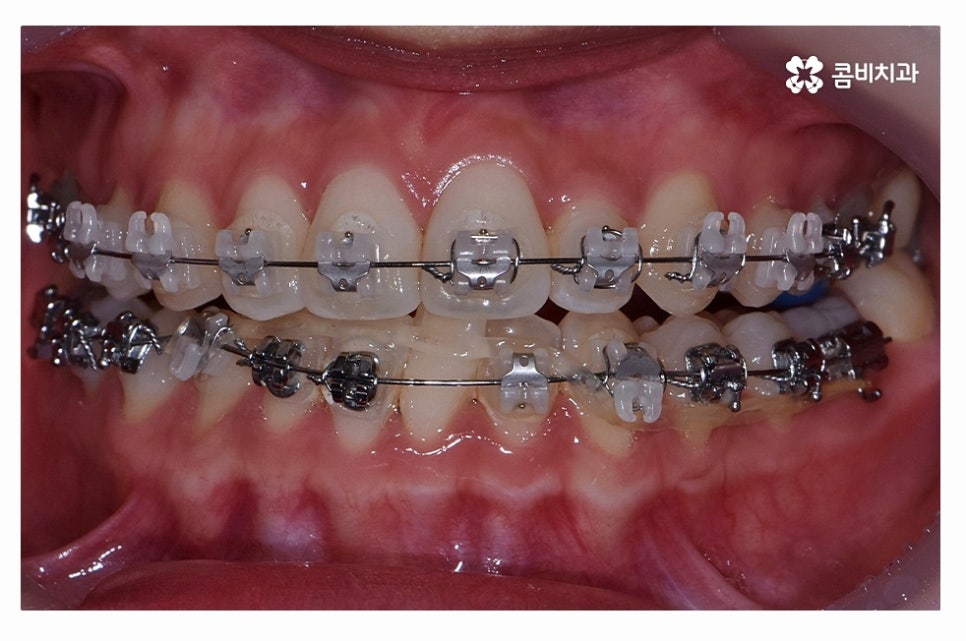

오늘 보여드릴 사례도 덧니교정이 비발치로 진행이 된 사례이며

치아의 이동 공간과 치아 상태, 골격, 얼굴형 등을

종합적으로 판단할 때 비발치로도 진행이 가능했던 사례라고 할 수 있어요.

교정 장치의 선택에 있어서는 다양한 교정 장치의 선택이 가능한데

심미성이 강조된 설측교정부터 콤비교정,

위 환자분의 사례처럼 클리피씨교정이 보편적으로 많이 활용되고 있는데요.

클리피씨교정은 치아의 이동이 일반 장치에 비해 상대적으로

빠르기 때문에 치료 기간이 단축될 수 있으며

통증의 감소, 내원 횟수를 줄일 수 있다는 장점 등이 있어요.